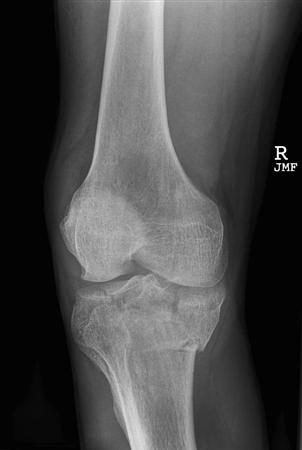

| Imaging |

- Radiographs

- recommended views

- AP

- lateral

- oblique

- oblique is helpful to determine amount of depression

- on AP

- depressed articular surface

- sclerotic band of bone indicating compression fx

- abnormal joint alignment

- on lateral

- posteromedial fracture lines must be recognized